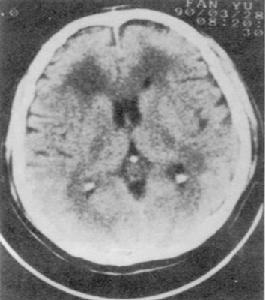

酒中毒性小腦變性酒中毒性小腦變性症是以運動失調為主要症狀病理學上是以小腦及其傳入、傳出途徑的變性為主體的疾病,臨床上是以肢體共濟失調和構音障礙為主要特徵。獲得型小腦變性後天的中毒性和代謝性原因引起的小腦變性和共濟失調。酒中毒性小腦變性是嗜酒者常見的小腦變性發病率約為Wernicke腦病的2倍臨床特點為步態不穩步距增寬。CT和MRI研究表明慢性酒中毒病人幾乎都有小腦萎縮小腦蚓部上端萎縮較重蚓部上端血流量減少和糖代謝率下降明顯。

診斷:根據慢性酒中毒的病史典型的小腦共濟失調的症狀體徵CT或MRI發現小腦蚓部上端萎縮排除其他原因的小腦萎縮和小腦變性家族史,診斷即可成立。

其它輔助檢查:1.心電圖、腦電圖腦CT或MRI檢查有鑑別診斷及中毒程度評估意義;2.肌電圖和神經電生理檢查有鑑別診斷意義。